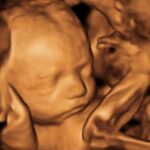

Ofrecemos servicios de ecografía obstétrica avanzada (genética, estructural, Doppler) y seguimiento experto de embarazos de alto riesgo, utilizando tecnología de punta para diagnósticos precisos